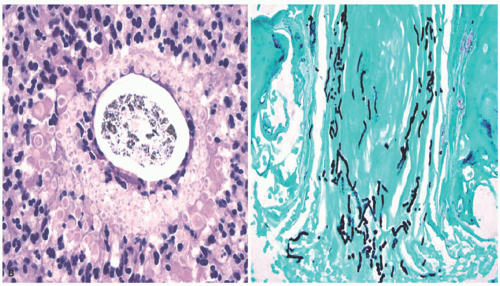

The causative organisms invade the stratum corneum and then involve hair follicles, extending into the shafts to the level of the mid-follicle. Endothrix infections are defined as those showing intrapiliary hyphae or arthrospores. Endo-ectothrix infections are those that exhibit fungal elements within and around altered hair shafts. In the superficial dermis, the inflammatory response varies from scant perivascular lymphocytic infiltration to dense and diffuse effacement of the corium by acute and chronic inflammatory cells in kerion (Figure 20-2). Neutrophils are commonly seen in the stratum corneum. Rupture of hair follicles may provoke a granulomatous response.

![]() FIGURE 20-2. (continued) B, Acute and chronic inflammation surrounds infected hair follicles in kerion (left panel). A GMS stain demonstrates intrafollicular fungal organisms. |